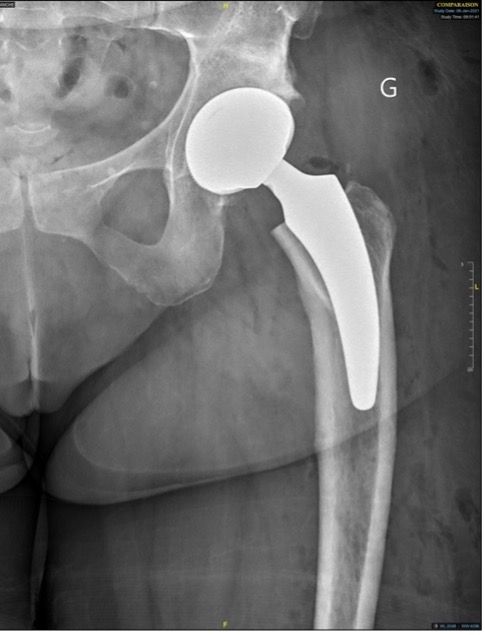

Hips in coxa vara sometimes present a very significant femoral offset which may be prove to be difficult to restore using standard stems. In this case, a varus-tilted or lateralized stem should be used and this will require a very low femoral cut, often with loss of residual femoral offset and a risk of lengthening the lower limb. Positioning a straight cementless stem in varus runs the risk of trajectory error and femoral pain. If a modular neck implant is chosen, the increased lever arm results in significant pressures on the modular neck and neck-head junction with risks that are already known. Finally, even with a cemented stem, positioning it in varus will increase the pressures on the bone-cement interface, with a risk of early loosening. With calcar-guided short stems, the stem will follow the medial cortex of the neck (which will have been cut high), naturally finding a varus tilt and making it possible to reproduce even very significant offsets (Figs 4 and 5).